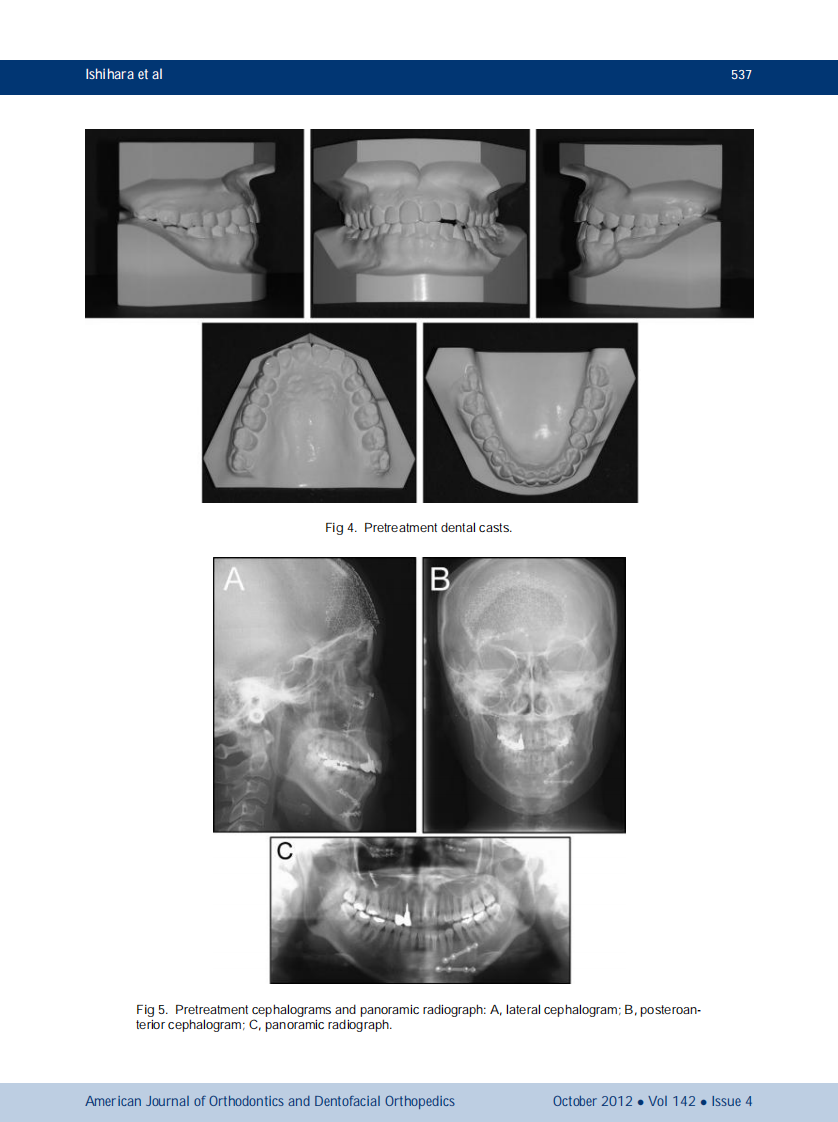

AJO-DO

1-s2.0-S088954061200635X-main.pdf